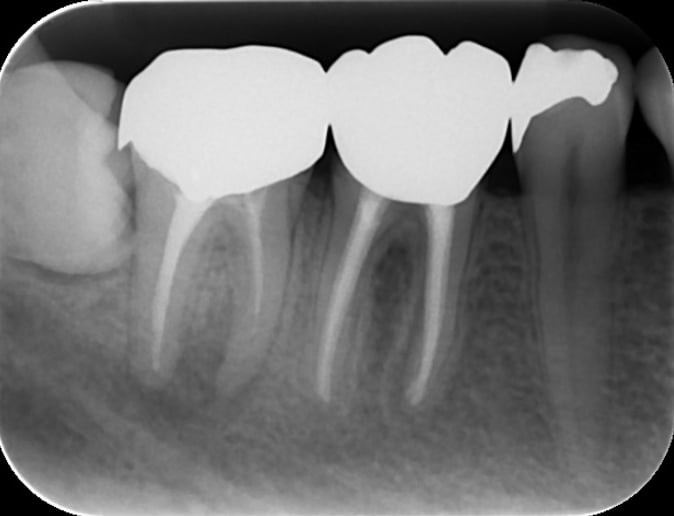

A comparison of survival of teeth following endodontic treatment performed by general dentists or by specialists

Bradley S Alley, DMD, G Gray Kitchens, DMD, Larry W Alley, DMD, Paul D Eleazer, DDS, MS

Oral Surgery,Oral Medicine,Oral Pathology,Oral Radiology,and Endodontology Volume 98, Issue 1, July 2004, Pages 115-118